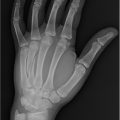

Complete, likely simple, syndactyly involving right long and ring fingers.

Simple/complex

Simple syndactyly: Finger fusion only by a skin bridge.

Complex syndactyly: Finger fusion involving bone connection.